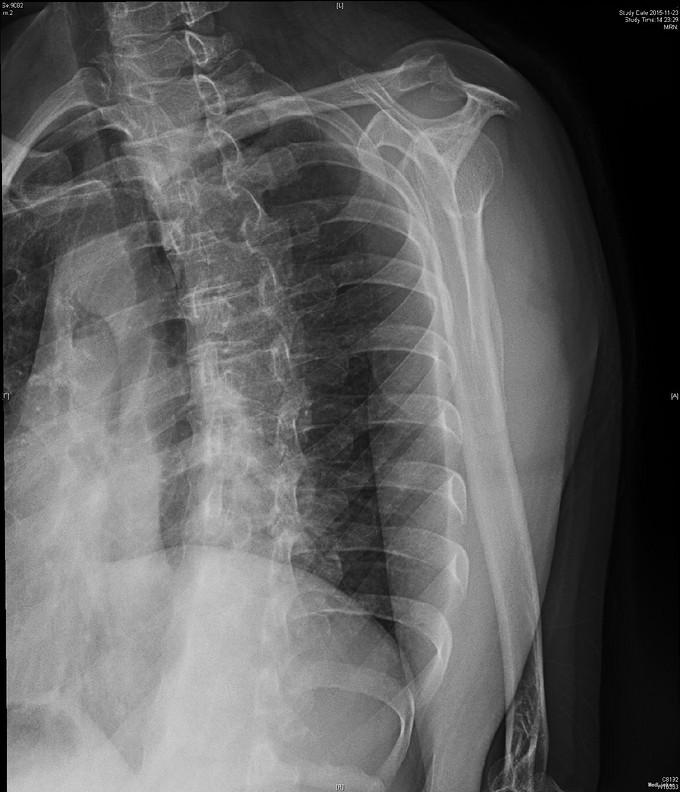

主诉:右肩疼痛5月,加重伴活动受限2月余。 现病史:患者,女性,45岁。5月前无明显诱因下出现右肩关节疼痛不适症状,偶伴有夜间痛,经休息等保守治疗后现疼痛症状略缓解。后患者至外院就诊,予口服药物等保守治疗,效果不佳,且有加重趋势。2月余前患者自觉右肩疼痛较前明显,伴活动受限。外院行MRI检查示:右肩关节内积液、右肩峰骨质增生、右肩袖肿胀、右肩盂唇信号异常。后患者来我院就诊,查右肩X线示:右肩峰前外侧见一骨性突起。门诊结合病史及体征,诊断“右肩峰下撞击综合症、右肩峰占位”收入院,行进一步治疗。

查体:右肩关节周围肌肉萎缩,右肩周压痛(+),右肩前方压痛(+),无明显肿胀。右肩关节主被动活动度明显受限,Hawking征(+),Neer征(+),Jobes征(-),Speed(+),O’brein征(-),Drop Arm(-)、熊抱试验(-)。外展肌力(Ⅳ)级。双上肢感觉正常。 辅查:见现病史,图片见下。

入院诊断:右肩峰下撞击综合症、右肩峰占位 治疗:右肩关节镜下肩峰成形,占位切除术